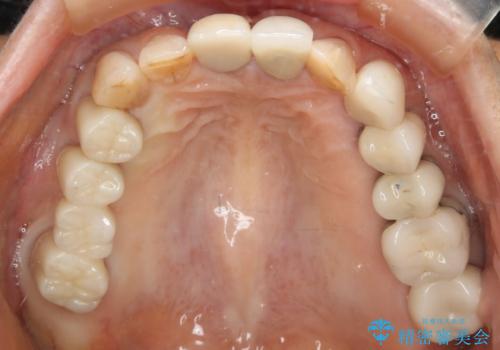

[ 総合歯科診療 ] がたつきの改善とセラミック治療

![[ 総合歯科診療 ] がたつきの改善とセラミック治療の症例 治療後](https://seimitsushinbi.jp/wp/wp-content/uploads/2024/03/7212917eb9c4ef33050c52e7f9724490-500x350.jpg?v=1710833188)